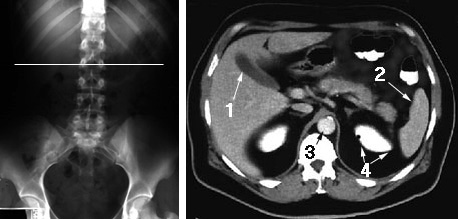

Another major advantage of CT over radiography is the ability to see structures and organs that blend together in a common shade of gray on a radiograph. For example: a radiograph of the abdomen will not demonstrate the gallbladder, because the liver, which the gallbladder is superimposed on, is the same shade of gray,

A section of the abdomen on a CT scan through the liver and gallbladder will show them both in dramatic detail. This is due to the fact that the detectors of the CT are more sensitive to changes in the x-ray beam than a radiographic film, and the CT computer is able to enhance those changes after they are recorded.

The CT image dramatically demonstrates organs and tissues that are all similar shades of gray on the radiograph. No. 1 is the gallbladder surrounded by the liver; No. 2 is the spleen; No. 3 is the abdominal aorta; and No. 4 is the upper pole of the left kidney.